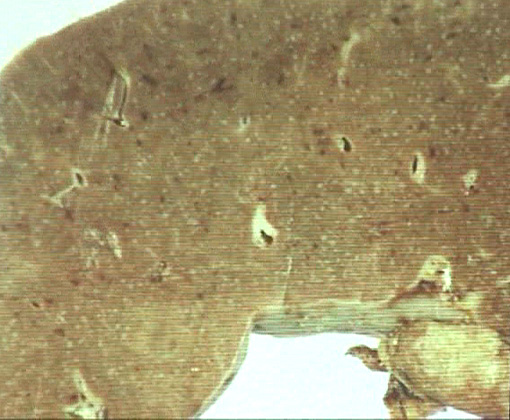

腋窩リンパ節生検組織病理所見(右図)

萎縮したリンパ濾胞が散在, 胚中心はリンパ球に乏しくFDC陽性の紡錘形細胞がトグロを巻いているように存在し周囲の血管進入像もある。濾胞間には血管が増生, リンパ球は減少している。

萎縮した胚中心にはFDCが詰まっておりMantle zoneリンパ球は残っている。これら所見からは, もともとは胚中心をもつ大きな濾胞であったものがリンパ球が抜けて萎縮した。あたらしいリンパ球がhomingしていないのではないかと考えられる。

リンパ節のCastleman病に類似する病変。--->1. リンパ節, 低倍率, 2. リンパ節濾胞 Sorry, 閲覧にはID, passwordが必要です